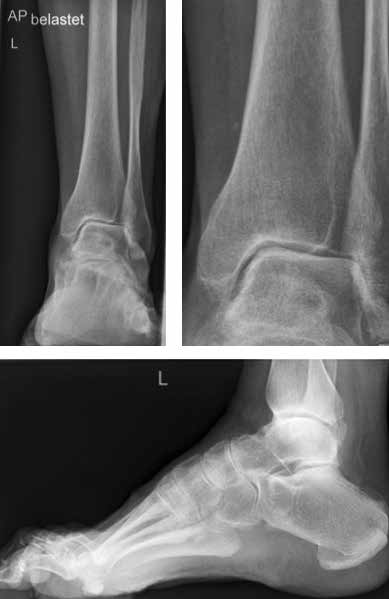

Primäres radiologisches Verfahren ist die konventionelle Röntgendiagnostik des oberen Sprunggelenkes unter Belastung mit dem eigenen Körpergewicht. Hierbei können bereits unterschiedlich stark ausgeprägte Gelenkdestruktionen diagnostiziert werden. Neben der Gelenkspaltverschmälerung können Osteophytenbildung und subchondrale Sklerosierung sowie Zystenbildung erhoben werden. Die Klassifikation nach Morrey/Wiedemann basiert auf diesen radiologischen Befunden 19: